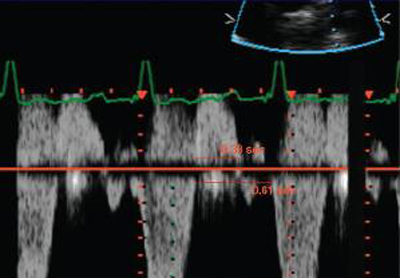

Doppler em um paciente com regurgitação pulmonar após reparo de tetralogia de Fallot. O paciente tem ventrículo direito restritivo e o Doppler mostra evidências de restrição com onda "A" anterógrada na artéria pulmonar

De: Chaturvedi RR, Redington AN. Heart. 2007 Jul;93(7):880-9; usado com permissão